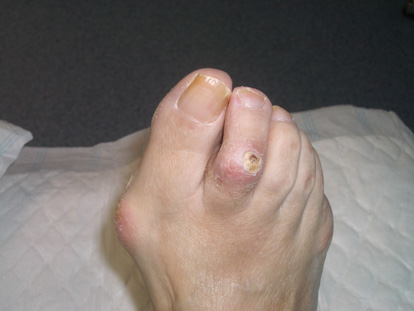

Imatge real pre-operatòria